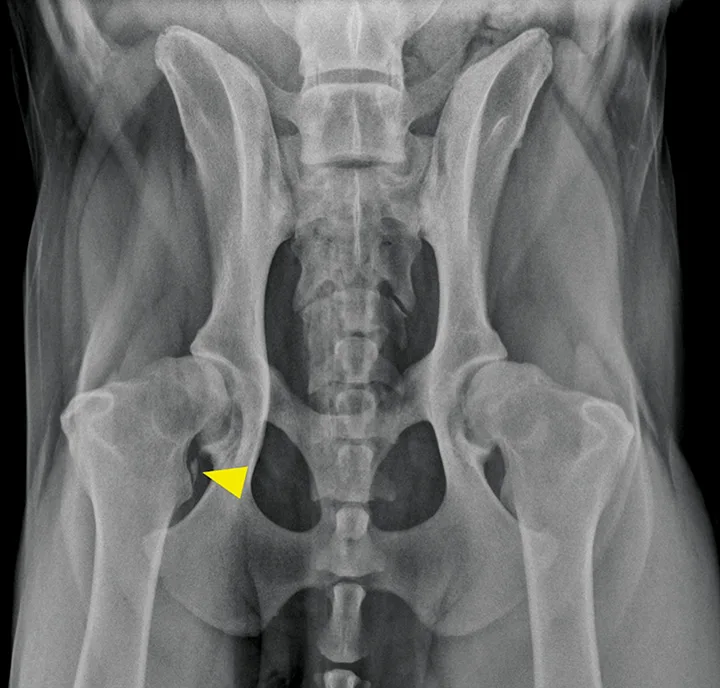

The iliopsoas muscle consists of the iliacus and psoas major muscle groups, which originate along the lumbar spine and ilium and insert on the lesser trochanter of the femur. Its main function is to flex and externally rotate the hip. Injury can occur secondary to an acute excessive force or repetitive use and/or trauma, resulting in a mild-to-severe pelvic limb lameness.7-10 Pain often can be elicited on examination by extension and internal rotation of the hip joint, abduction of the femur, and direct palpation of the muscle–tendon junction near the lesser trochanter.7-10 Because the femoral nerve runs through the iliopsoas muscle, some dogs that strain this muscle may also develop a peripheral neuropathy from compression of the nerve.8,9 Standard radiography can identify mineralization in the tendon, whereas ultrasonography, CT, and MRI are helpful for identifying early and subtle lesions and can help direct therapy (Figures 5 and 6).8-10 Mild-to-moderate acute lesions can often be treated with medical management (eg, rest, NSAIDs, physiotherapy, platelet-rich plasma injections).10 If the lesion is severe and results in fibrosis or contracture of the muscle, a partial tenectomy may be indicated.8,10

FIGURE 5

Ventrodorsal radiographic projection of a 9-year-old dog with right hindlimb lameness and hip pain. In addition to bilateral hip dysplasia and secondary osteoarthritis, mineralization is present within the right iliopsoas muscle near the tendon insertion on the lesser trochanter (arrowhead), which indicates a chronic strain injury.